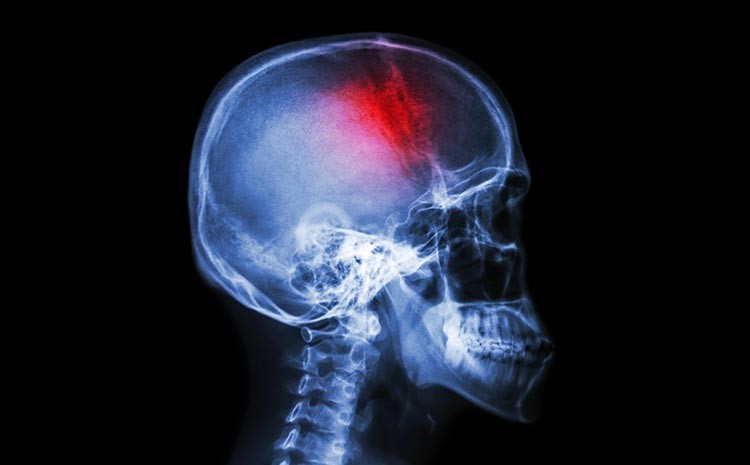

O cérebro sob pressão silenciosa

O cérebro depende de um fluxo constante de sangue para funcionar. Quando esse fluxo é interrompido, como no AVC isquêmico, ou quando há sangramento, como no hemorrágico, inicia-se uma corrida silenciosa contra o tempo.

Não se trata de um dano imediato e uniforme. Existe uma área mais comprometida e outra ao redor que ainda resiste. Essa região intermediária, muitas vezes invisível para quem observa de fora, é onde existe potencial de recuperação — e onde o tempo exerce maior influência.

O paciente não percebe exatamente esse processo acontecendo. Mas, do ponto de vista clínico, cada minuto sem intervenção pode significar perda progressiva de funções importantes, como movimento, fala e autonomia.

É por isso que, nas primeiras horas, o tempo deixa de ser abstrato. Ele passa a ser um fator concreto na preservação daquilo que ainda pode ser salvo.